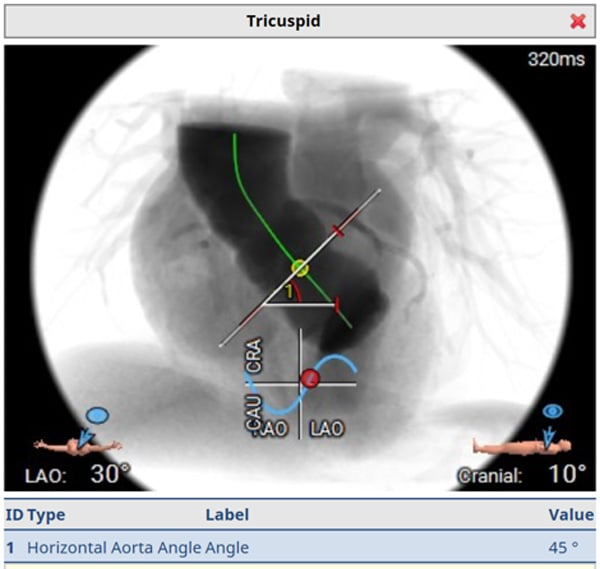

Computed tomography